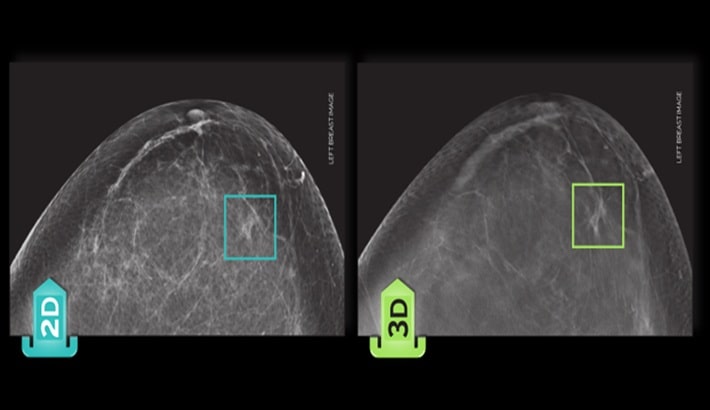

ماموگرافی یکی از دقیقترین روشهای تصویربرداری برای بررسی سلامت پستان است؛ این روش در شیراز با دو تکنولوژی اصلی : ماموگرافی دیجیتال و ماموگرافی سهبعدی یا توموسنتز انجام میشود. بسیاری از افراد هنگام مراجعه برای «مامو» یا «مامو گرافی»، نمیدانند تفاوت این دو روش چیست؟ و کدام گزینه برای بررسی دقیقتر انتخاب بهتری است؟ شناخت مزایا، محدودیتها و کاربردهای هر روش به تصمیمگیری بهتر کمک میکند و باعث میشود ارزیابی پستان با دقت بیشتری انجام شود.

ماموگرافی دیجیتال چیست؟

ماموگرافی دیجیتال نسل جدیدتر ماموگرافی قدیمی است که در آن تصاویر با دقت بالا و بهصورت دیجیتال روی مانیتور ثبت و بررسی میشوند. این روش استاندارد طلایی برای غربالگری پستان است و در اغلب مراکز تصویربرداری شیراز بهصورت روتین انجام میشود.

در این روش دو تصویر اصلی از هر پستان تهیه میشود و رادیولوژیست، هرگونه توده، تغییر بافتی یا ناهنجاری را ارزیابی میکند.

مامو دیجیتال نسبت به ماموگرافیهای قدیمی مزایای زیادی از جمله وضوح بهتر، دوز کمتر اشعه و امکان بزرگنمایی دقیقتر بخشهای مشکوک دارد. اما هنوز یک محدودیت اصلی دارد؛ تصویر نهایی دوبعدی است و در خانمهایی که بافت سینه متراکم دارند، گاهی تشخیص تودههای کوچک یا مخفی دشوار میشود.

ماموگرافی سهبعدی (توموسنتز) چیست؟

ماموگرافی سهبعدی یا (DBT) نسل پیشرفتهتر ماموگرافی دیجیتال است. در این روش دستگاه از زوایای مختلف چندین تصویر نازک (اسلایسمانند) از پستان تهیه میکند؛ سپس سیستم کامپیوتری این تصاویر را بهصورت یک مدل سهبعدی بازسازی میکند.

به همین دلیل رادیولوژیست میتواند لایهبهلایه بافت پستان را ببیند و ناهنجاریها را بدون همپوشانی بافتها تشخیص دهد.

نوع تصویر و دقت تشخیص

در مامو دیجیتال، تصویر بهصورت دوبعدی ثبت میشود؛ یعنی تمام لایههای بافت روی هم قرار میگیرند. این موضوع گاهی تشخیص دقیق را سخت میکند.

در توموسنتز، تصاویر بهصورت چندلایه و سهبعدی هستند. بافتهای پستان از هم جدا میشوند و این موضوع احتمال تشخیص زودهنگام ضایعه را بهطور چشمگیری افزایش میدهد. در نتیجه ماموگرافی سهبعدی معمولاً دقت بسیار بیشتری در کشف تودهها، بهخصوص تودههای کوچک دارد.